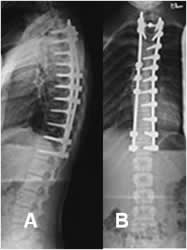

En la escoliosis idiopática de adolescentes y adultos, está indicada la cirugía para curvas mayores de 45º. La cirugía también está indicada en la escoliosis congénita progresiva, pacientes que no toleran el corsé o cuyas curvas progresan, a pesar de su utilización. (8). (Fig 41, 42 y 43).

Fig 41. Corrección quirúrgica.

A: Rx lateral y B: Rx AP. Corrección de escoliosis dorsal, mediante barras posteriores.

Fig 42 A. Corrección quirúrgica.

A: Rx lateral y B: Rx AP. Corrección de escoliosis dorsolumbar izquierda, mediante placas laterales.

Fig 42 B. Corrección quirúrgica.

A: Rx AP y B: Rx lateral. Fijación de escoliosis dorsal derecha, por medio de barras.